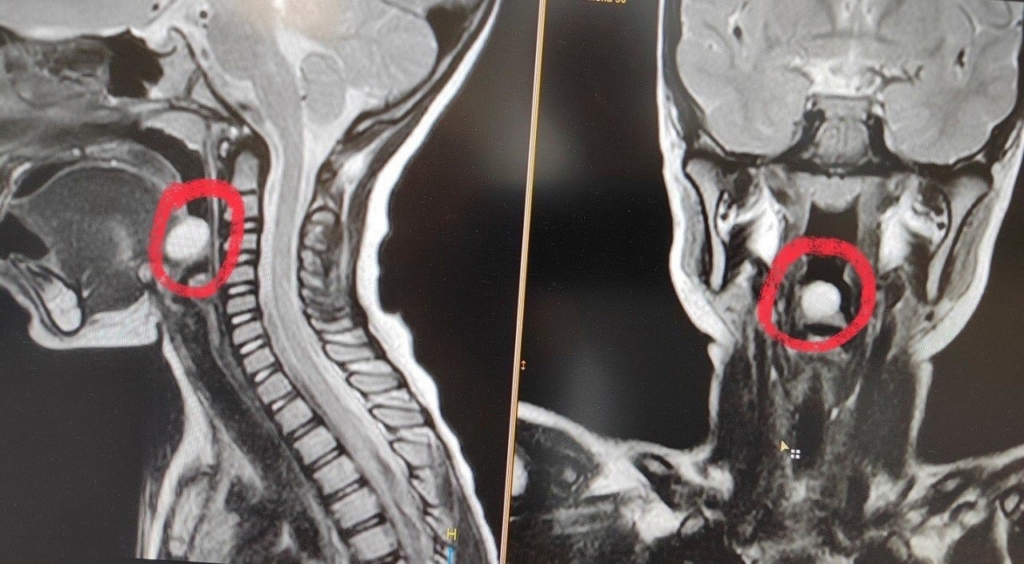

В начале года в оториноларингологическое отделение Воронежской областной детской клинической больницы №1 (ВОДКБ №1) поступила 5-летняя девочка с жалобами на затруднение при глотании. При профилактическом осмотре ЛОР-врач заподозрил новообразование надгортанника и направил в дневной стационар онкогематологии ВОДКБ №1. Там врачи провели ребенку эндоскопическое обследование и МРТ с контрастированием, что позволило определить диагноз: киста надгортанника. Медики приняли решение об эндоскопическом удалении новообразования.

Врачи отметили, что киста надгортанника является достаточно редкой патологией в детской оториноларингологической практике. В России таких случаев описано совсем немного. А в практике ВОДКБ №1 это и вовсе единственный случай за последние 15 лет.